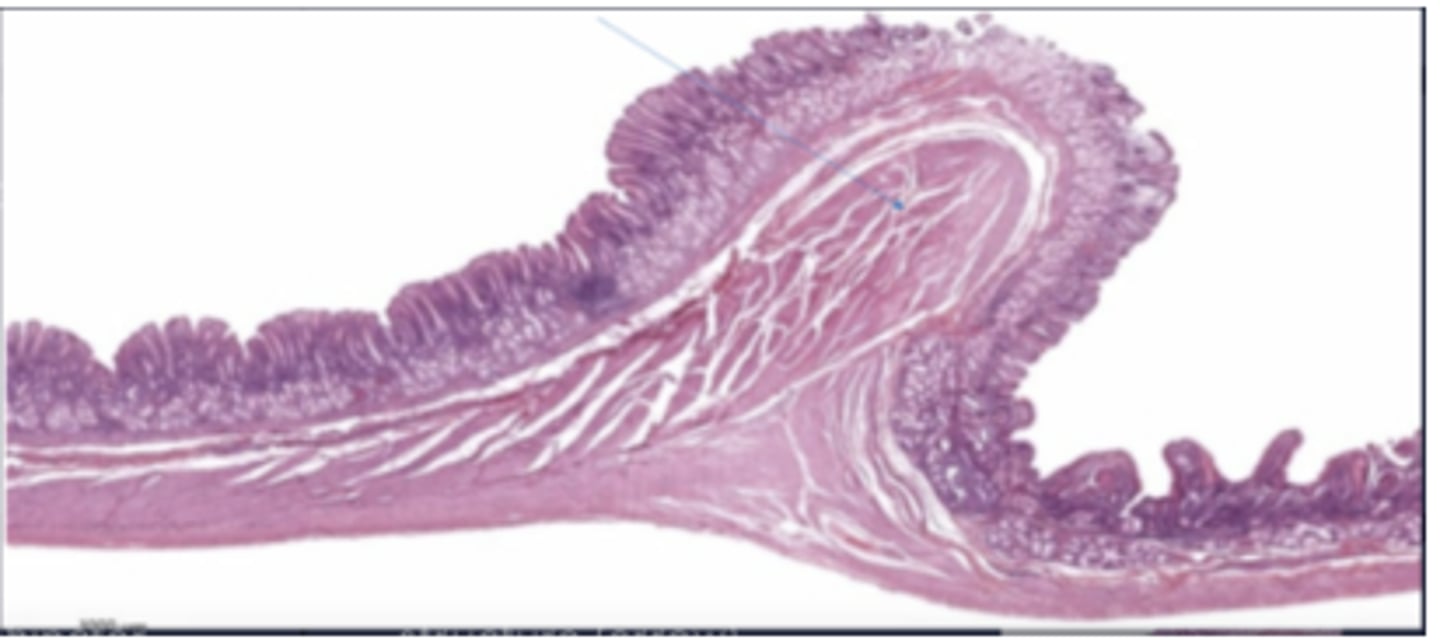

ureter

transitional/urothelium

What kind of epithelium is in the ureter?